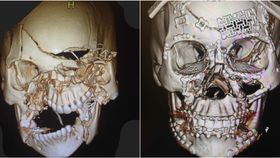

Images have recently resurfaced online that show the incredible reconstruction of a woman’s face, and the Internet is freaking out.

The rest of this article is behind a paywall. Please sign in or subscribe to access the full content.Posted on the medical website Figure 1, a physician by the username "sidsid" impressed users by doing the seemingly impossible: He patched together a patient’s face with a mixture of metal wires, plates, and screws in a surgery that lasted eight hours.

The woman, 25, in question was allegedly involved in a serious motor collision in which she wasn’t wearing a seatbelt. She entered the emergency room with "traumatic brain injury with intracranial hemorrhage, a traumatic eye injury requiring enucleation, and extensive facial fractures," reports the Metro.

The ophthalmologist and his team worked tirelessly to perform a procedure to not only save the woman’s life, but also reconstruct her bone structure.

The surgeon commented in an update afterwards, saying the patient still has "traumatic brain injury. Tracheostomy issues. C. Diff infection. Vertebral artery dissection management. Possible traumatic optic neuropathy of remaining eye," and that her jawbones were required to be wired shut for an extended period post-op.

He later said: "Just saw the patient in clinic today. She is very depressed but remarkable how she is recovering. Completely alert and oriented and walking."

Understandably, Figure 1 users took to the comments to express a mixture of awe, congratulations, and humpty-dumpty jokes. "You and your team are definitely wiser and more gifted than all of the King's men because you have surely put all of the pieces together again. Just phenomenal."

Many others were simply astounded at the skill and mastery of the surgeons. One user said: "The surgeons who performed this are an absolute team of da Vinci's’ (@PoiBaloo)."

@Shelly2919 posted: "Literally spectacular. Medicine at its finest right there!"

The images were posted to the site around two years ago, but have resurfaced across the Internet recently. The patient has now recovered, and the surgeon now periodically posts similar (albeit slightly less dramatic) work they are currently doing.

Hats off to you, sidsid – truly astonishing work.